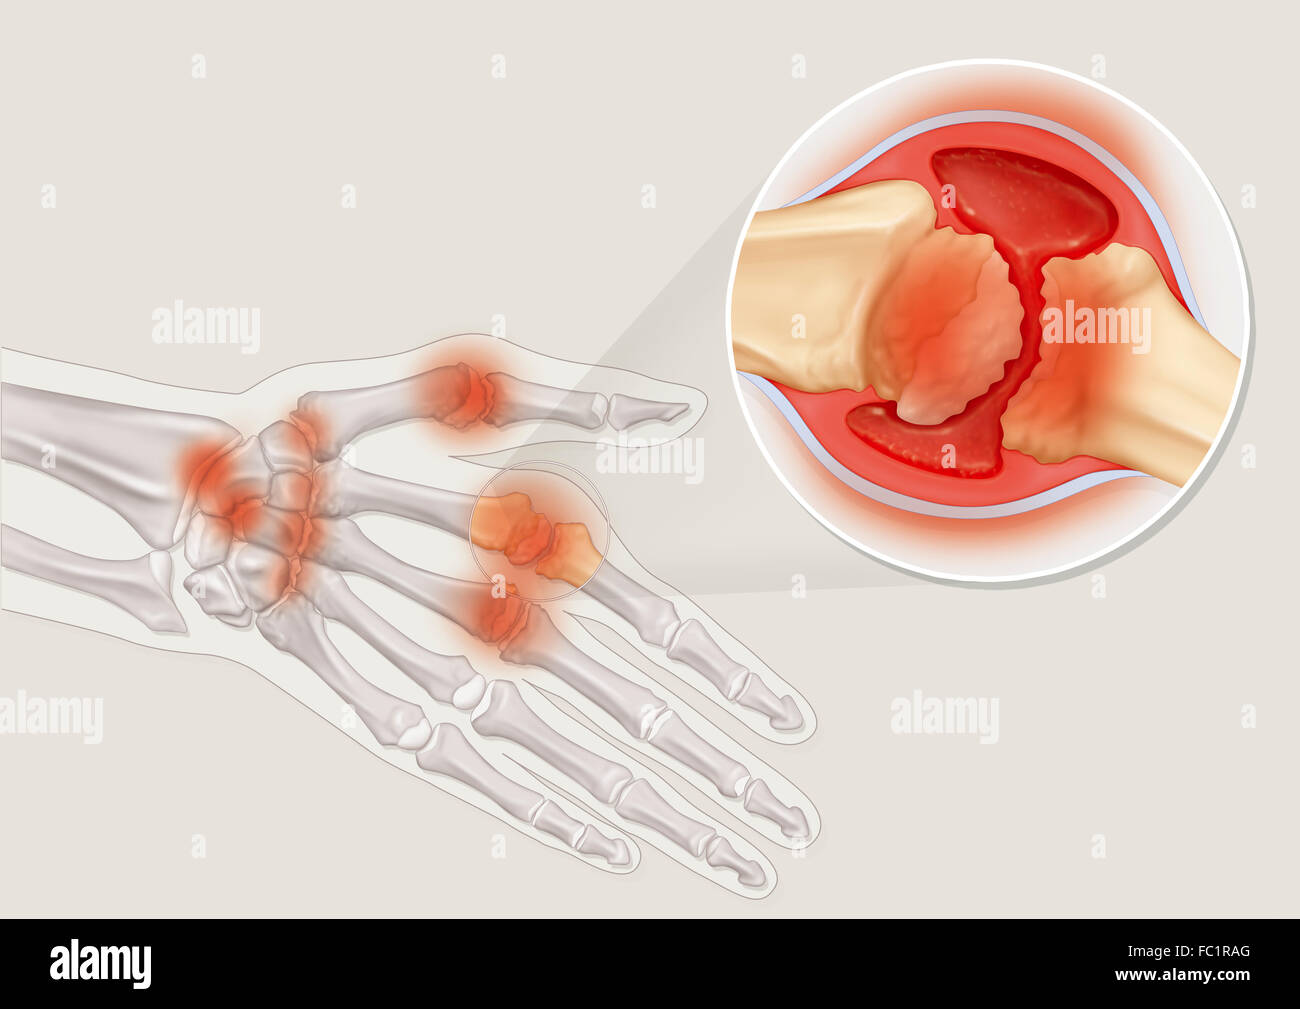

RHEUMATOID ARTHRITIS, DRAWING Stock Photohttps://www.alamy.com/image-license-details/?v=1https://www.alamy.com/stock-photo-rheumatoid-arthritis-drawing-93467992.html

RHEUMATOID ARTHRITIS, DRAWING Stock Photohttps://www.alamy.com/image-license-details/?v=1https://www.alamy.com/stock-photo-rheumatoid-arthritis-drawing-93467992.htmlRMFC1RAG–RHEUMATOID ARTHRITIS, DRAWING

RHEUMATOID ARTHRITIS, DRAWING Stock Photohttps://www.alamy.com/image-license-details/?v=1https://www.alamy.com/stock-photo-rheumatoid-arthritis-drawing-93467977.html

RHEUMATOID ARTHRITIS, DRAWING Stock Photohttps://www.alamy.com/image-license-details/?v=1https://www.alamy.com/stock-photo-rheumatoid-arthritis-drawing-93467977.htmlRMFC1RA1–RHEUMATOID ARTHRITIS, DRAWING